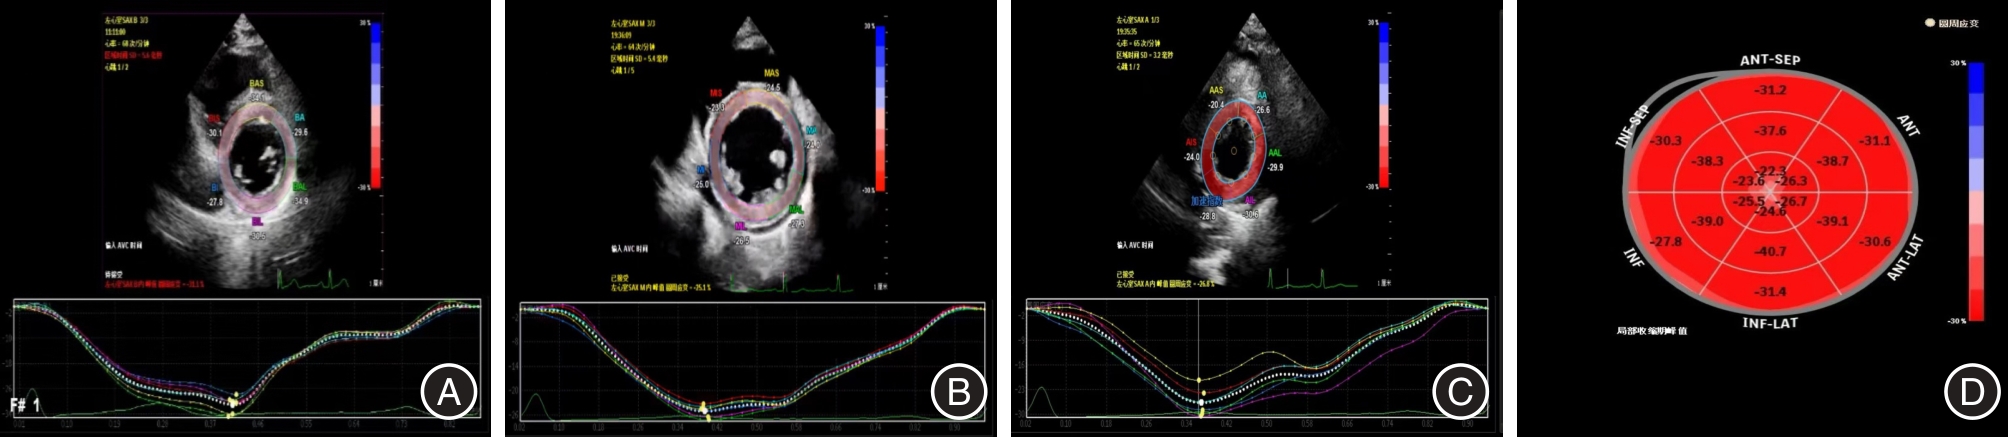

目的 应用自动心肌运动定量技术(aCMQ)评价2型糖尿病(T2DM)合并肾功能不全(CKD)患者的左室收缩功能并探讨其与临床生化指标的相关性。 方法 纳入80例T2DM患者,分为DM组(不合并CKD,n = 40)和DN组(合并CKD,n = 40),另外选取40例健康志愿者作为对照组,记录所有受试者的一般临床资料,并且行常规超声心动图和aCMQ技术检查,获取常规超声测量值和 aCMQ相关参数。 结果 aCMQ相关参数比较:三组左室整体纵向应变(LVGLS)、左室心尖两腔心纵向应变(LVAP2LS)、左室心尖三腔心纵向应变(LVAP3LS)、左室心尖四腔心纵向应变(LVAP4LS)差异均有统计学意义(P < 0.05)。DN组左室整体环向应变(LVGCS)与另外两组相比差异均有统计学意义(P < 0.05)。左室短轴基底段环向应变(LVSAXBCS)、左室短轴中间段环向应变(LVSAXMCS)、左室短轴心尖段环向应变(LVSAXACS)差异均无统计学意义(P > 0.05)。左室应变参数与高敏C反应蛋白(hs-CRP)、糖化白蛋白(GA)、糖化血红蛋白、肌酐、尿素及尿酸呈负相关,而与肾小球滤过率(eGFR)呈正相关。其中hs-CRP、GA和eGFR与左室应变参数之间有较好的相关性。 结论 aCMQ技术可早期发现T2DM合并CKD患者左室功能的恶化,通过左室应变参数与hs- CRP、GA和eGFR的相关性有助于更好地评估其心脏受累情况。

Objective To evaluate the left ventricular systolic function of patients with type 2 diabetes mellitus (T2DM) combined with renal insufficiency (CKD) by applying automated myocardial motion quantification (aCMQ) and to investigate its correlation with clinical biochemical indexes. Methods 80 patients with T2DM were enrolled, divided into DM group (without CKD, n = 40) and DN group (with CKD, n = 40), and 40 healthy volunteers were selected as the control group. The general clinical data of all subjects were recorded, and routine echocardiography and aCMQ were performed to obtain routine ultrasonographic measurements and aCMQ-related parameters. Results Comparison of aCMQ-related parameters: The differences in LV global longitudinal strain (LVGLS), LV apical 2-chamber longitudinal strain (LVAP2LS), LV apical 3-chamber longitudinal strain (LVAP3LS), and LV apical 4-chamber longitudinal strain (LVAP4LS) among the three groups were all statistically significant (P < 0.05). The differences in LV global circumferential strain (LVGCS) between the DN group and the other two groups were statistically significant (P < 0.05). The differences in LV short-axis basal segment cyclic strain (LVSAXBCS), LV short-axis middle segment cyclic strain (LVSAXMCS), and LV short-axis apical segment cyclic strain (LVSAXACS) were not statistically significant (P > 0.05). LV strain was negatively correlated with Hs- CRP, GA, HbA1c, creatinine, urea, and uric acid, and positively correlated with eGFR. Correlation. High-sensitivity C-reactive protein (Hs-CRP), glycated albumin (GA) and eGFR showed good correlation with LV strain parameters. Conclusion The aCMQ technique can detect the deterioration of left ventricular function in patients with type 2 diabetes mellitus combined with renal insufficiency at an early stage, and the correlation between left ventricular strain parameters and hs-CRP, GA and eGFR can help to better assess their cardiac involvement.